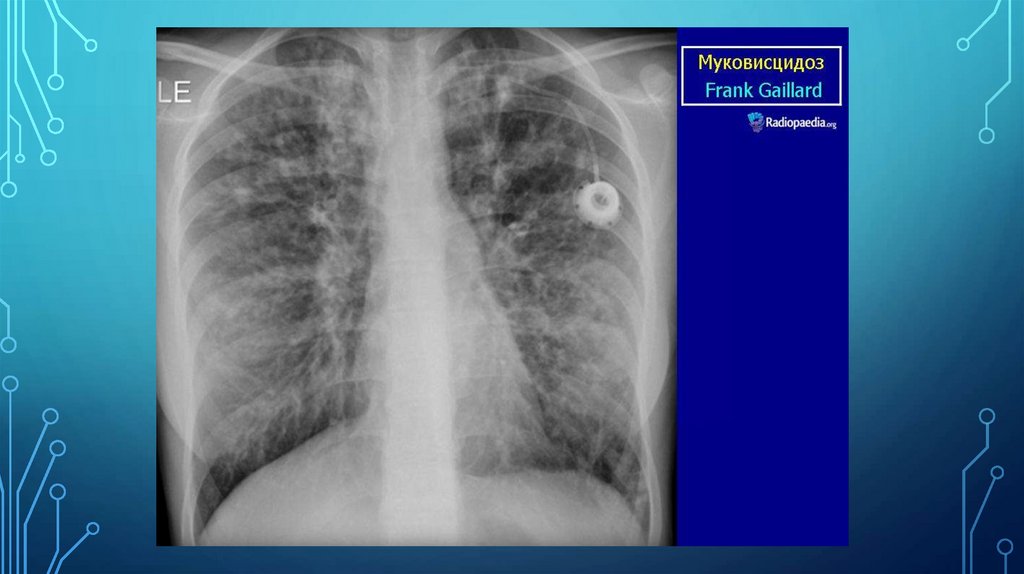

• 5) Рентгенологические: деформация и усиление легочного рисунка,

перибронхиальная инфильтрация, бронхоэктазы, буллы, очаги пневмосклероза.